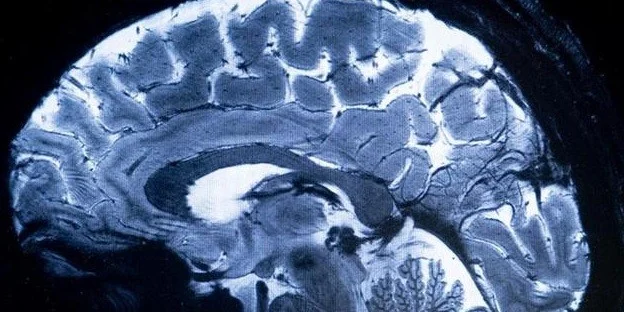

A Organização Mundial da Saúde (OMS) pediu nesta terça-feira (14), em caráter de urgência, mais atenção às doenças neurológicas, muitas delas preveníveis ou tratáveis, que afetam mais de três bilhões de pessoas.

As doenças neurológicas afetam mais de 40% da população mundial e provocam mais de 11 milhões de mortes a cada ano, segundo a OMS. As dez condições neurológicas que mais contribuem para a morte e a incapacidade são o acidente vascular cerebral, a enxaqueca, a doença de Alzheimer e outras demências, a meningite e a epilepsia idiopática, segundo os dados mais recentes disponíveis, de 2021.